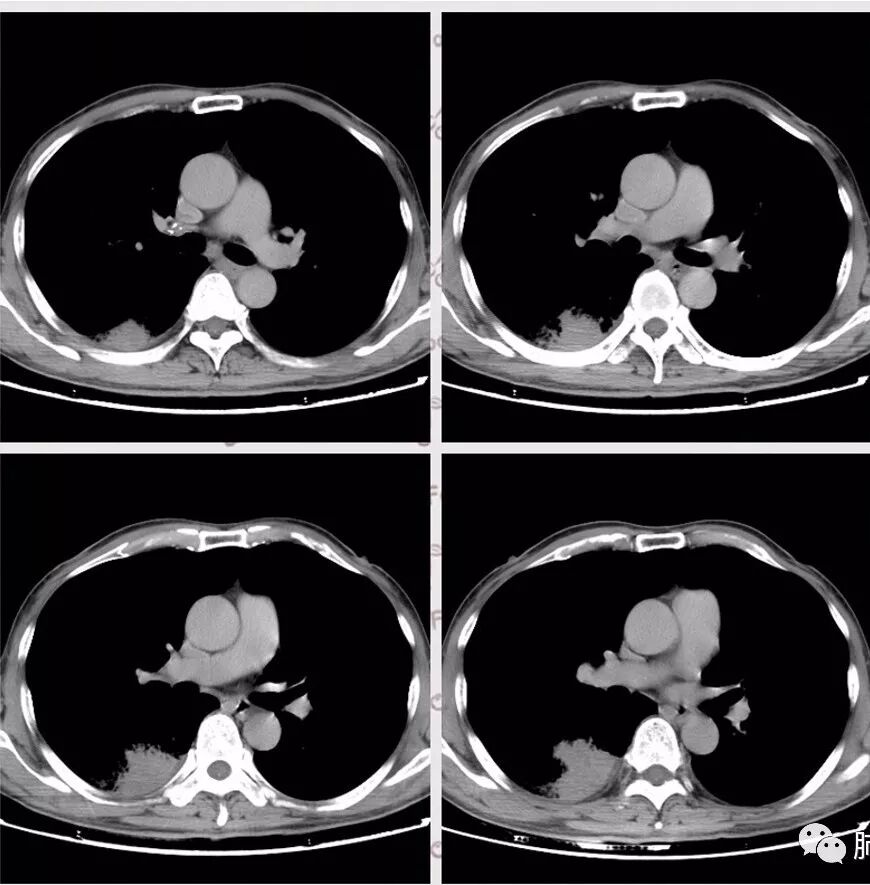

脑内多发结节,DWI壁弥散受限,腔不受限

强化内外壁部分区域稍毛糙

颅内环形的高信号,但是可以发现这个的DWI环是厚的,但是增强扫描的环是非常薄的,如果是肿瘤的,就是壁的弥散受限是肿瘤细胞的话,那么他强化的环应该跟DWI的环的厚度是一样的,所以这个环形的低DWI高信号应该是脓肿。而且就是关于这个脓腔壁的,就是脓腔的外壁是非常模糊的,而内壁还是相对光整,环不是很完整。下面一个图,没有给到,DWI上可以看到沿着破溃的脓肿壁向外侵出去的感觉,如果是环形转移的,那么它的那个内壁是更加不光整,而外壁是相对比较清楚一些的。

这个颅内病灶增强扫描的无强化区范围与DWI高信号范围是一致的,所以还是脓腔内受限,至少时期不那么典型,不是纯粹的高信号,DWI是厚层、增强是薄层;而且扫描角度也不一样,所以无法完全对上

脓肿内的坏死、脓液形成也不是一次性完全形成的,就像在肝脓肿内,信号也是不一致的。重点还是在于强化区的地方弥散受限了还是无强化区的地方受限了,还是那句话,强化壁比弥散壁薄很多,无强化区比弥散不受限区范围大多了

3.脑内多发混杂信号病灶,显著长T1、显著长T2信号为主。注意TW1及TW2均显示环形等密度影(这在转移瘤是非常罕见的)且出现相应的环形强化。中央液化区DW扩散受限以及周边广泛水肿等,都符合典型多发脑脓肿改变。

4.脓腔较大,也更符合细菌感染。(脑内结核、隐球菌及奴卡菌感染病灶通常不易有如此大范围)

综上患者符合肺脓肿及脑脓肿诊断,病原菌以肺炎克雷伯杆菌等感染可能性较大